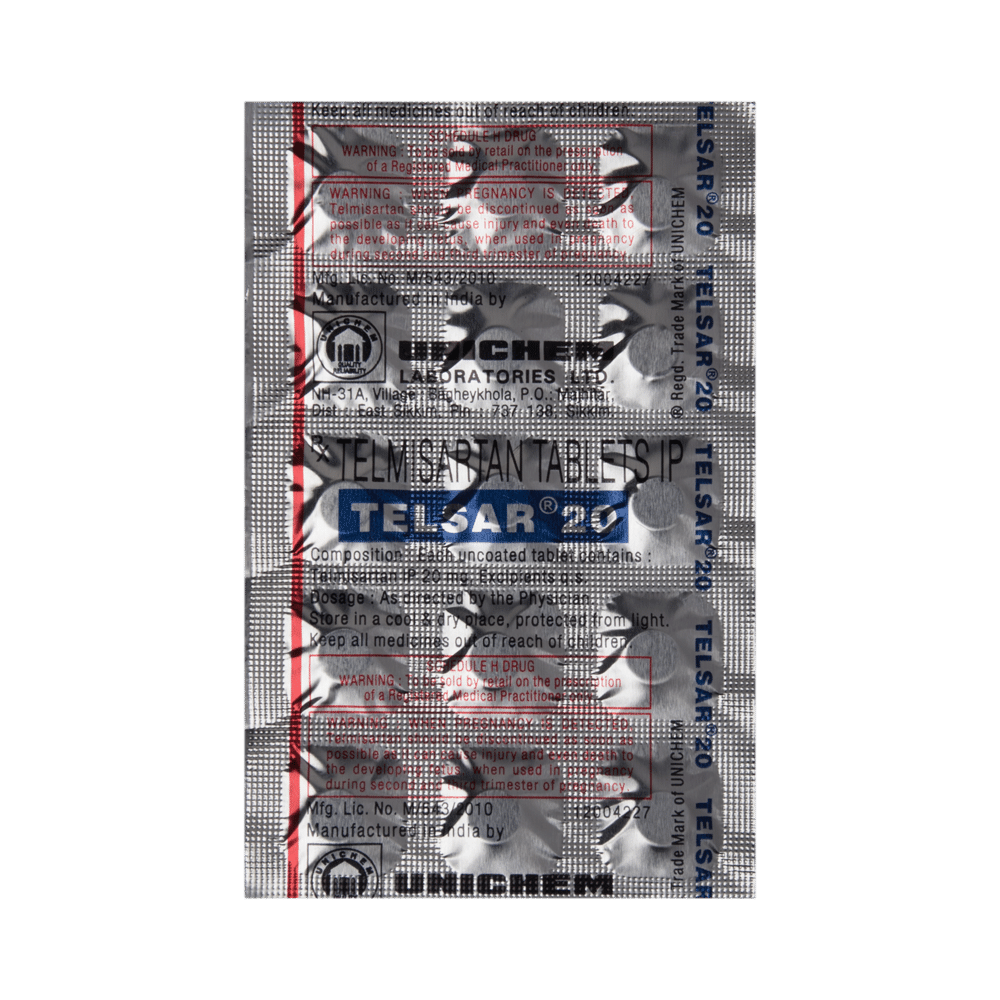

| Salt Composition: | Telmisartan (20mg) |

| Manufacturer: | Torrent Pharmaceuticals Ltd |

Telsar 20 Tablet is unsafe to use during pregnancy as there is definite evidence of risk to the developing baby. However, the doctor may rarely prescribe it in some life-threatening situations if the benefits are more than the potential risks. Please consult your doctor.